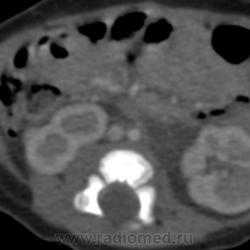

Девочка, 1 месяц, по УЗИ - кисты в области верхнего полюса левой почки. Сделали КТ, кисты оказались уретерогидронефрозом верхней половины удвоенной почки, с отсутствием функции. А вот что за кальцинаты по ходу почечной вены???